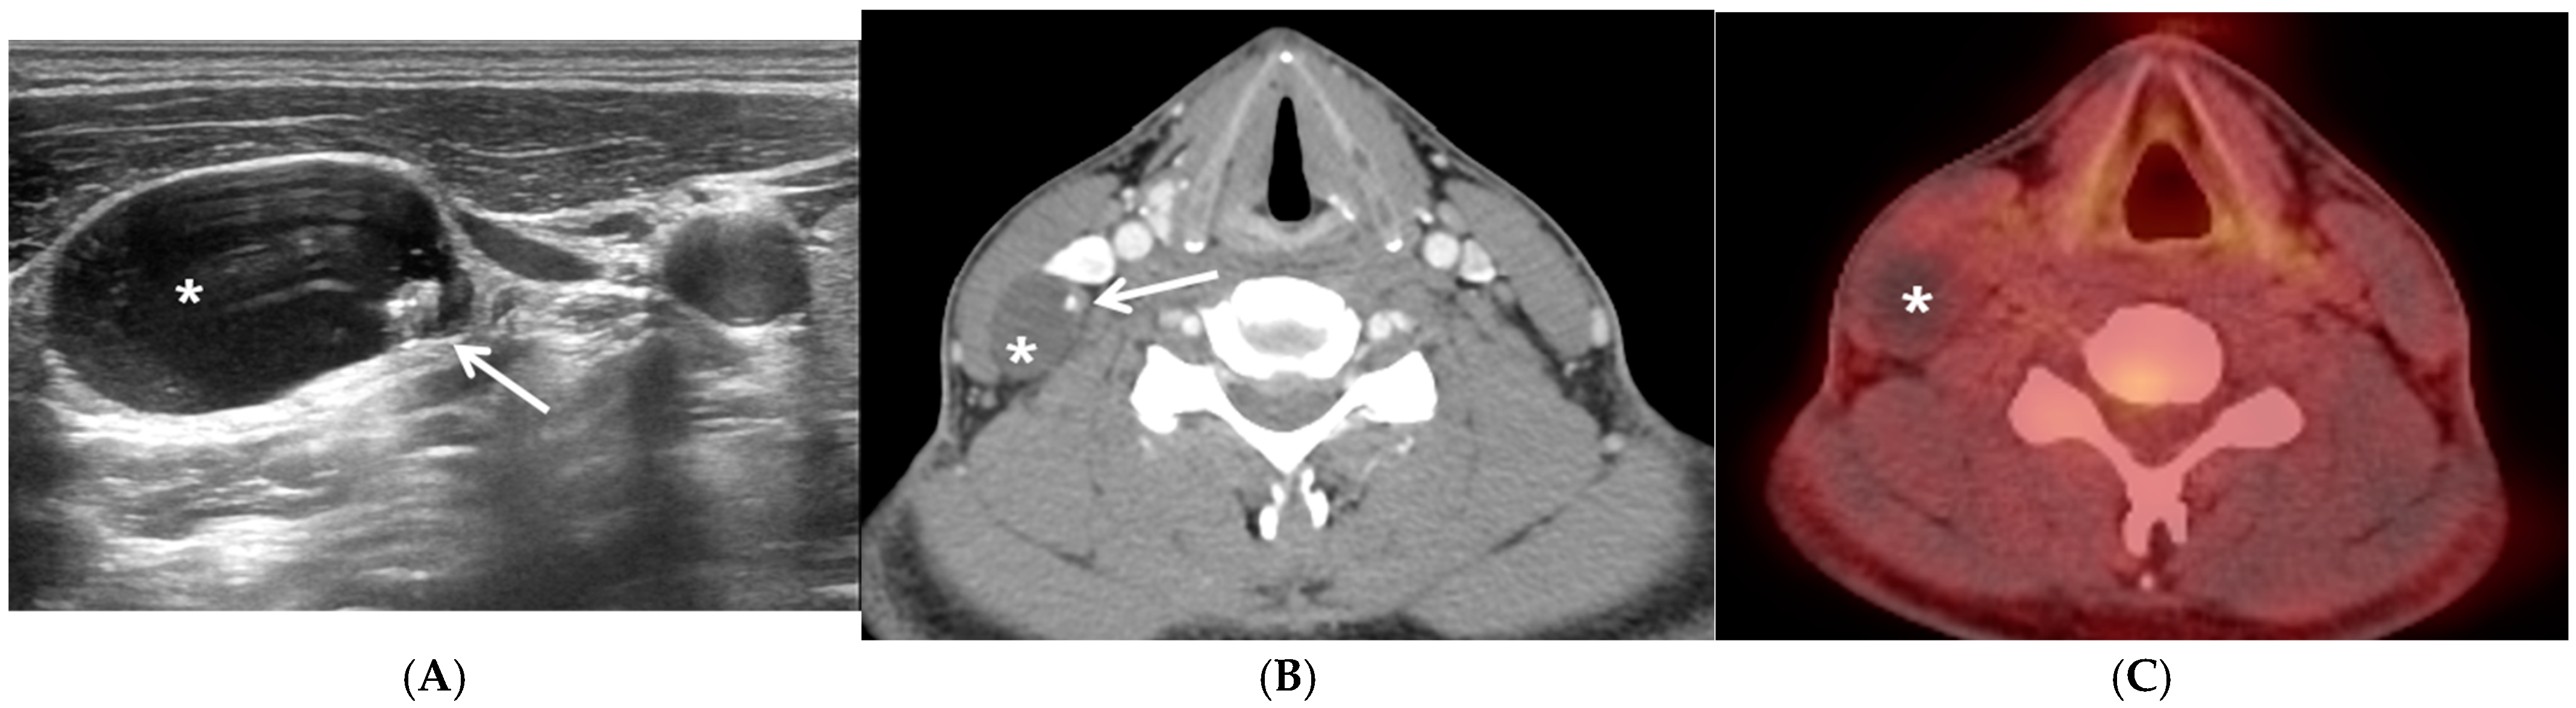

Thyroid Cancer Explore vol.3 no.2(2201 「Thyroid Cancer Expl。Thyroid Cancer | SpringerLink。Advances in Functional Imaging of Differentiated Thyroid Cancer。

Thyroid crisis caused by metastatic thyroid cancer: an

Thyroid crisis caused by metastatic thyroid cancer: an